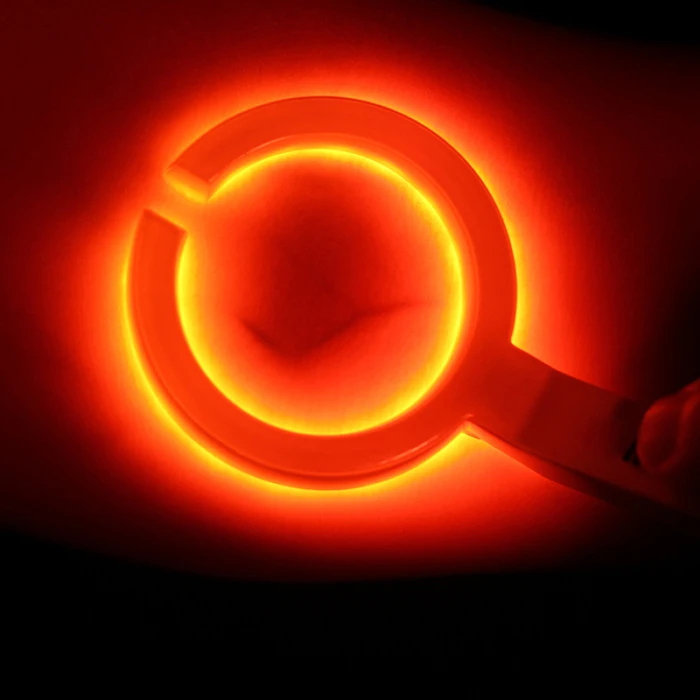

Взрослая детская визуализация инфракрасный васкулярный IV вены Finder Transilluminator вены просмотра TN88

Наше портативное устройство для просмотра Вены-Доступный портативный обнаружитель вен для общего доступа вены у взрослых и детей.

Питание от зарядного устройства непосредственно при использовании с 15 светодиодами, управляемыми одним переключателем.

Он используется для эффективного доступа IV в аварийной медицине.